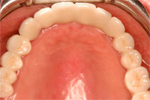

④ 上の顎。最終的なオールセラミックの歯が入ったところ。

⑤ 上下とも治療の終わった状態。メインテナンスに入ります。